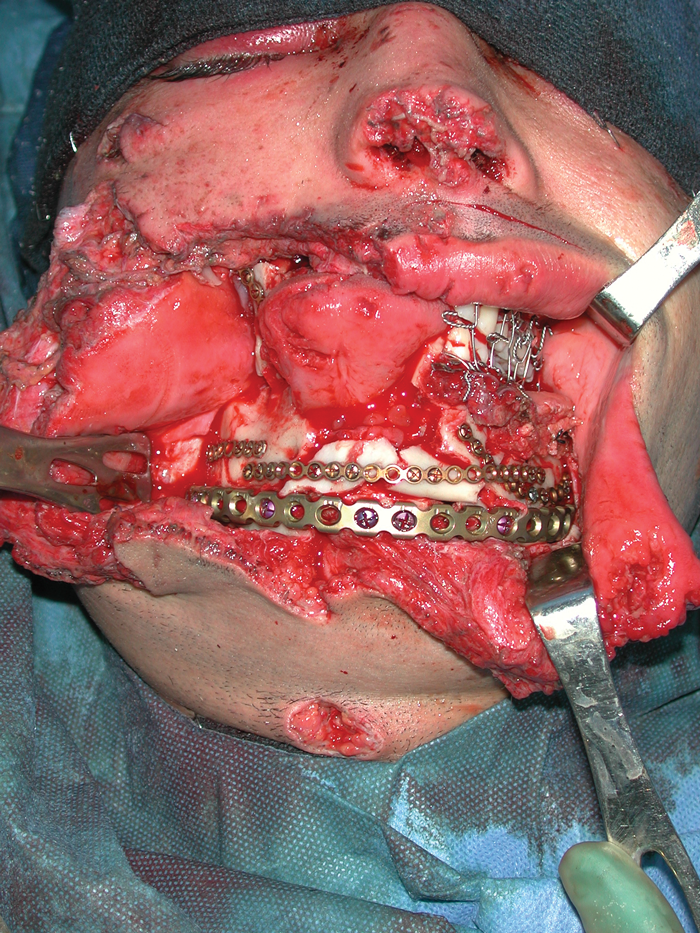

The role of the maxillo-facial surgeon in the management of skull base malignancy

Whilst ablative surgery remains the principal treatment option for head and neck malignancy, the skull base is the last frontier. The complex anatomy, supreme functionality of the brain, and varied pathology provokes many a detailed discussion in the multidisciplinary team...